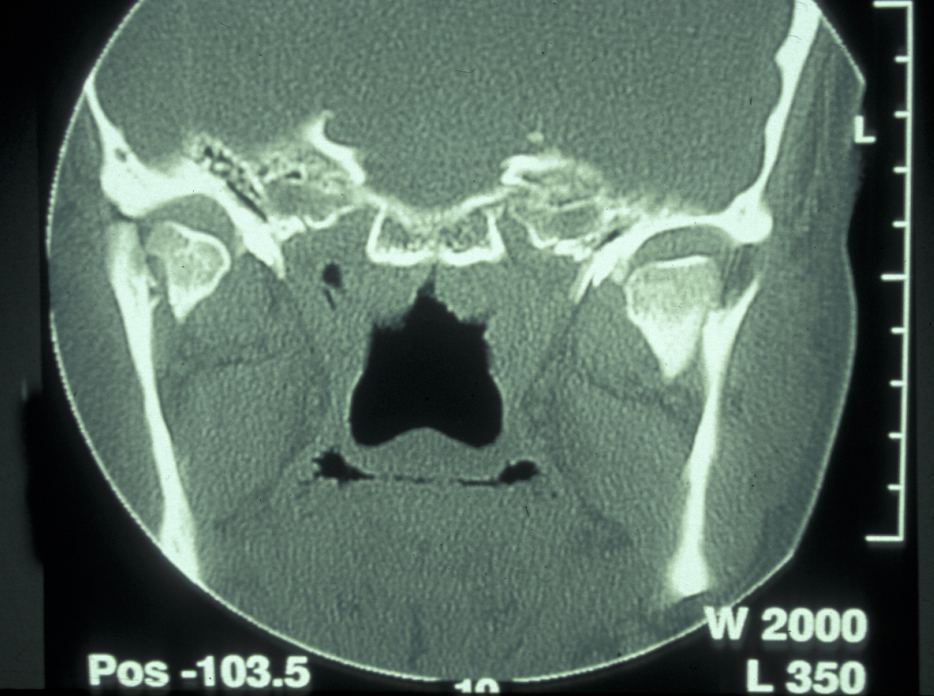

Plain film X-ray radiographs from different angles generally give sufficient diagnostic information. Combined they give good imaging of the zygomatic complex and can be used to determine the level of displacement and fracture pattern. Teardrop appearance into the maxillary antrum suggests an isolated orbital floor fracture (a 'blow out orbital fracture'; see Figure 8). Identification of this type of fracture mandates further investigation by a coronal (vertical plane view) CT scan and Hess chart test (eye test to assess motility of the eye).

Figure 8: A coronal CT scan showing a ‘blow-out’ fracture of the orbital floor.